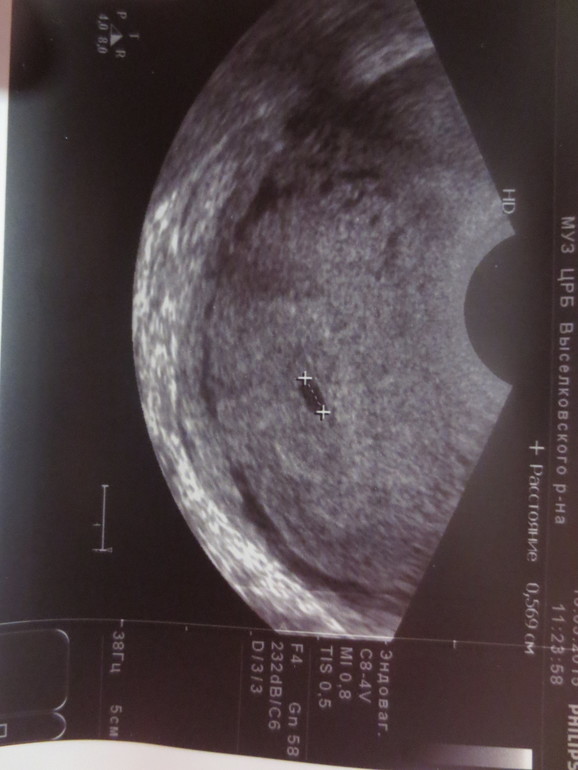

это сегодня, 6 ДЗ, в кресле нас не увидели, я позвонила узисту, он сказала. уже можно приходить, эндавагинальное узи с первой секунды осмотра определило Б

это наше первое фото)такое долгожданное!